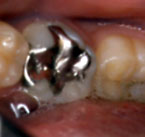

| 左下の第一大臼歯 |

右下の第一大臼歯 |

むし歯部分が

大きければ

大きく削ることに

なりますが、

若い人の歯は

やはり削らないほうが

いいでしょう。 |